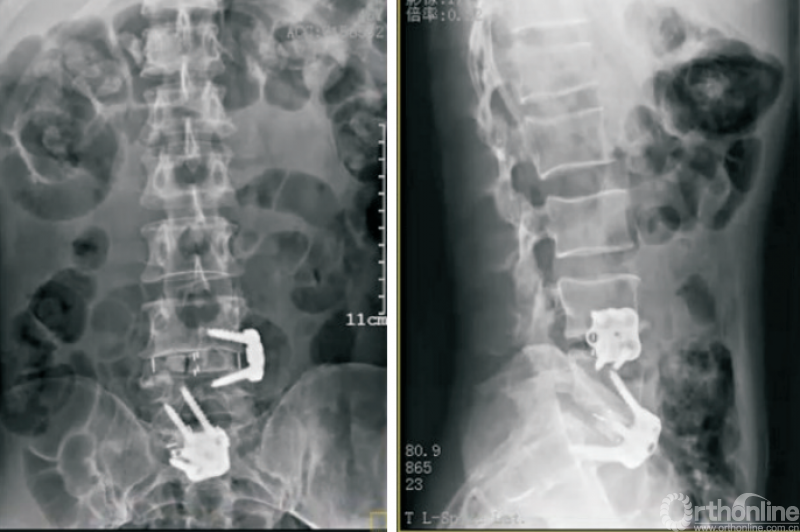

终板塌陷和融合器沉降(图6)是Stand-aloneOLIF的常见并发症,也是导致术后翻修的重要预测因素。融合器沉降与终板强度、手术操作以及解剖稳定性相关。终板硬化及形态平衡能够降低融合器沉降的发生率[36]。

图6 OLIF术后融合器沉降

LIU等[37]研究发现,在MRI影像中有Modic改变以及CT影像提示终板硬化的患者终板沉降的发生率明显低于其他患者。术中选择合适的融合器以及良好的脊柱稳定性也有利于降低融合器沉降的发生率[38]。ZHANG等[30]研究利用尸体标本模拟OLIF手术,通过研究生物力学特征、骨小梁微结构损伤等探索融合器与椎体骺环相对大小及位置对终板塌陷及融合器沉降发生率的影响,因此,在Stand-alone OLIF中选择合适的融合器对于减少终板塌陷及融合器沉降至关重要。

FANG等[39]通过构建有限元模型比较Stand-alone OLIF与OLIF联合后路钉棒系统固定两种手术方式后屈伸活动时终板应力等的变化,发现OLIF联合后路钉棒系统可降低屈伸活动时终板所承受的最大应力。术中终板损伤、间隙过度撑开等均会增大融合器沉降的发生风险。